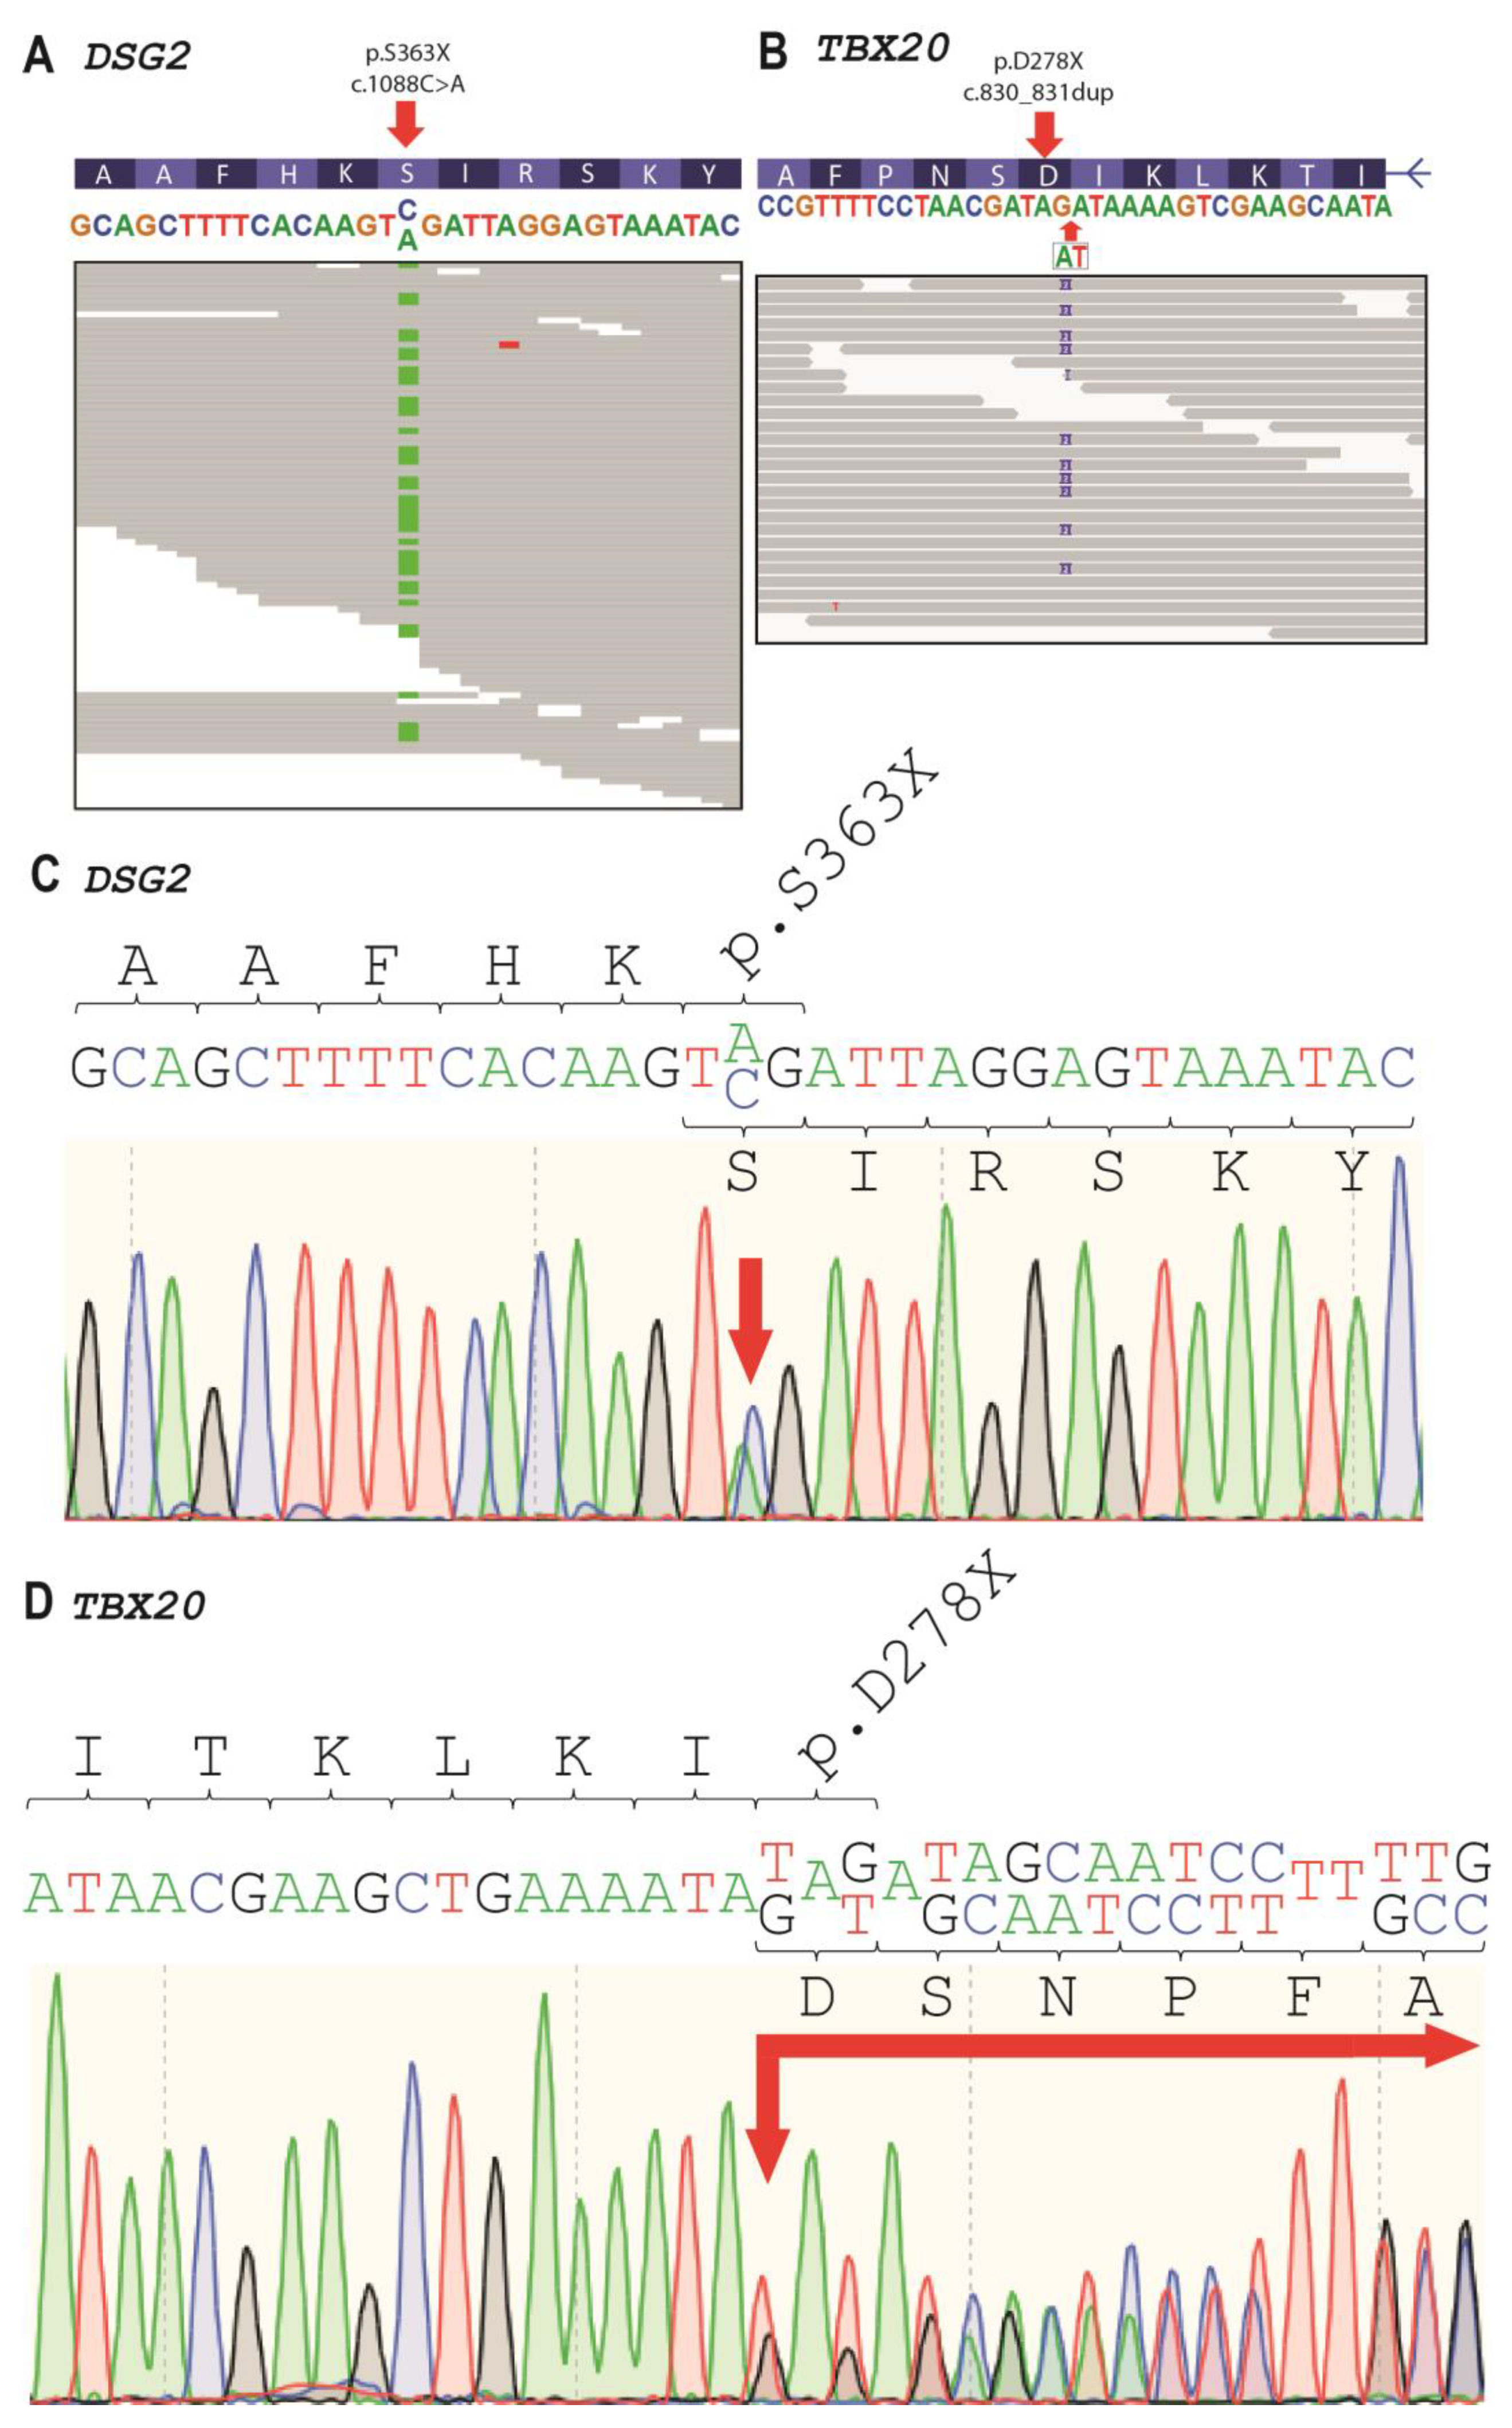

2.2. Genetic Analysis

4.4. Plasmid Generation

4.5. Cell Culture, Immunocytochemistry and Confocal Microscopy